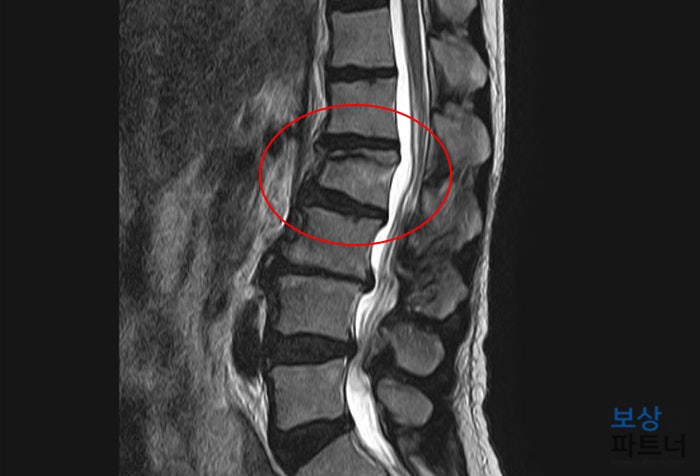

정밀 검사 결과 허리뼈의 골절 발생으로 확인되었는데요, 바로 요추 2번 압박골절이었습니다. L 님은 나이가 있으셔서 골밀도 검사가 필수였습니다. 검사 결과 BMD : -2.6 점수를 나타내셨는데요, 골다공증에 해당하는 수치였습니다.

이처럼 뼈가 약한 경우에는 추가적인 골절 진행이 생길 가능성이 크기 때문에 시술적 치료가 불가피하였는데요. 골절된 척추체에 골 형성제(포스테오) 주입하여 굳히는 시술인 일명 **"골시멘트술(척추체 성형술)"**을 시행하게 되었습니다.

위 사진처럼 골 형성제(골시멘트)가 단단하게 굳으면서 안정적으로 척추를 지지해 줄 수 있는데요. 골시멘트술은 성공적으로 끝나게 되었고, 이후에는 허리보호기(TLSO) 착용하면서 약 2~3개월간 안정을 취하게 되셨습니다.

골시멘트술(척추체 성형술)이 성공적으로 끝난 뒤에는 별다른 운동 장해나 후유증이 남지 않을 수 있는데요. 그런데 후유증상이 남지 않더라도 보험약관상 척추 골절 그 자체로기형 장해의 요건이 될 수 있습니다.

왜냐하면 한번 압박골절된 척추는 영구적으로 원상태로 돌아가지 않는데요. 이러한 골절로 인해 척추의 각도 변형이나 전만증 또는 후만증이 생기기도 합니다. 그러므로 후유장해보험이 있으시다면 아래의 척추의 기형 장해 지급률만큼 보험금 청구하실 수 있습니다.